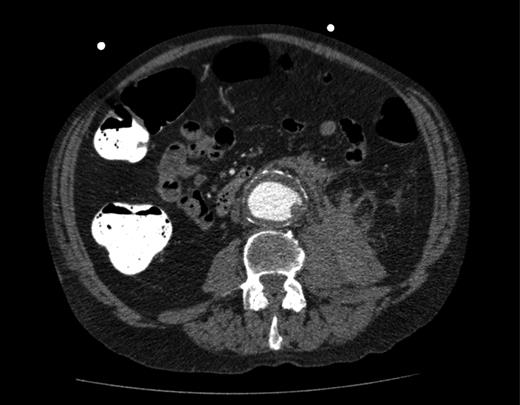

This time he was tachycardic and hypotensive with a much less distended but tender abdomen and still no palpable pulsatile masses. He was clinically stable enough to undergo a further CT scan of the abdomen and pelvis, now revealing a ruptured AAA (Fig. 4). We immediately transferred the patient to the regional hospital where he underwent emergency endovascular aneurysm repair on the same day.

Repeat CT scan of the abdomen, showing evidence of a contained rupture.